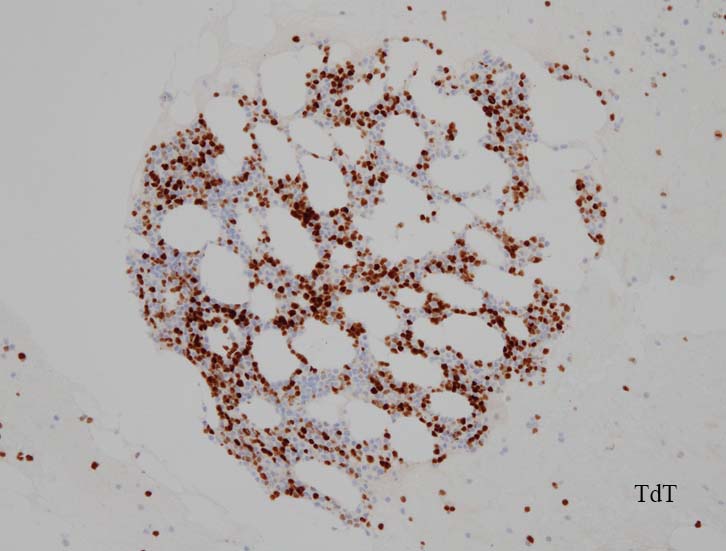

免疫染色

blastic cellsは, CD45+, CD34+, CD38+, TdT+, CD7+, HLA-DR+, CD123+. cCD3-, sCD3-(FCM), CD20-, CD19-とCD79a-(?) (plasma cellが陽性でIHCでは判定が難しい), MPO-.

CD3-, CD79aは増加しているplasma cellsが陽性で判定が難しい. CD10-, MPO-. (CD10は画像欠)